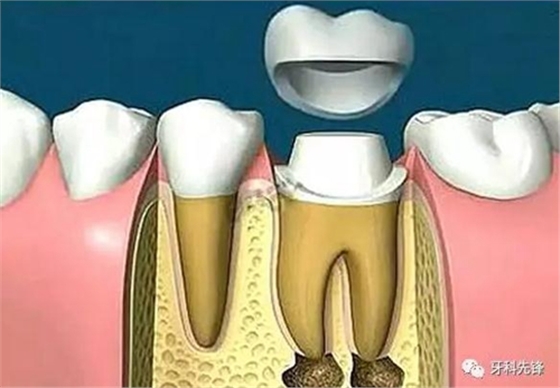

由于這3個(gè)方面的原因,整個(gè)牙齒的支持力量明顯減弱,可能在某些特定條件下不足以支持咀嚼壓力而容易發(fā)生牙冠劈裂,所以要及時(shí)做個(gè)牙冠把牙齒保護(hù)起來。

“戴冠”若不夠,樁釘來幫忙

當(dāng)牙齒做完根管治療,由于牙齒自身的結(jié)構(gòu)及治療的需要,牙冠中心一般都是空的,這時(shí),如果直接做牙套,其抗折斷力很差,一般都需要在牙根上打上樁釘,做出個(gè)結(jié)實(shí)的核,以對抗牙齒使用中的折斷力。